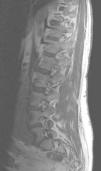

Fig. 2. Resonancia magnética ponderada en T2 (A) sagital línea media y (B) parasagital. En el espacio epidural anterior (A) y en los forámenes de conjunción (B) se aprecian estructuras vasculares con aspecto serpinginoso y arrosariado (flechas).